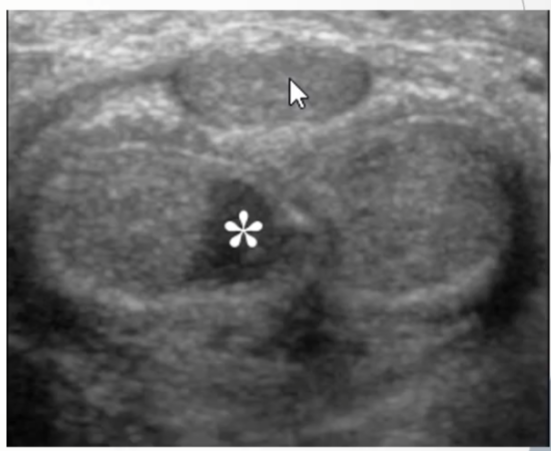

Longitudinal and Transverse images: Asterisk () demonstrates hypoechoic tumor which is confined to the subepithelial connective tissue and does not penetrate through or invade the tunica albuginea of the corpus cavernosa (arrows)*